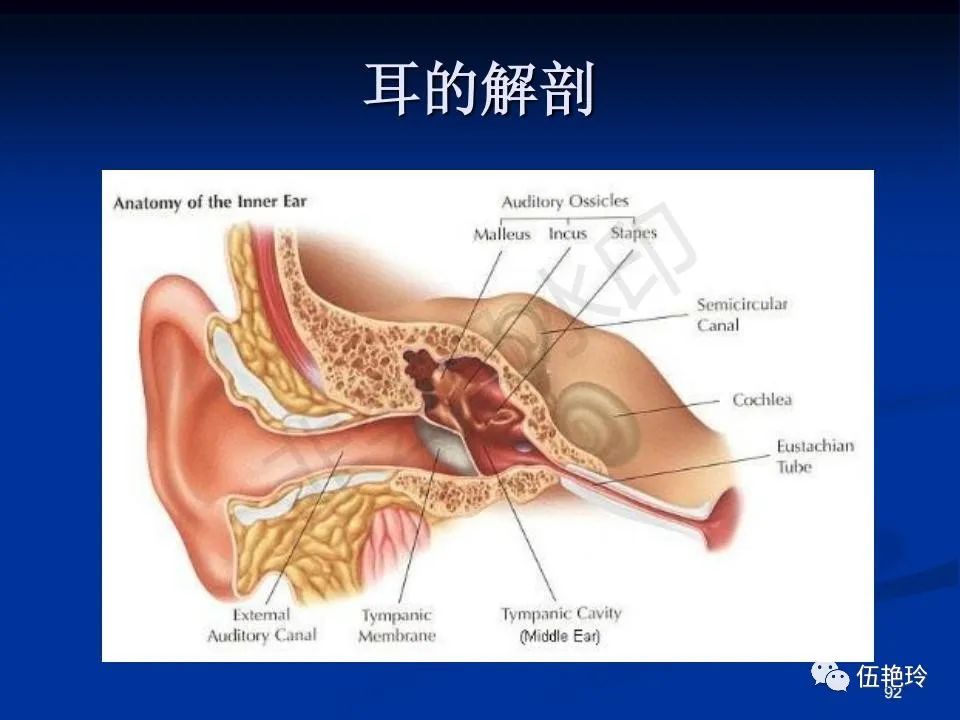

耳与面神经的解剖